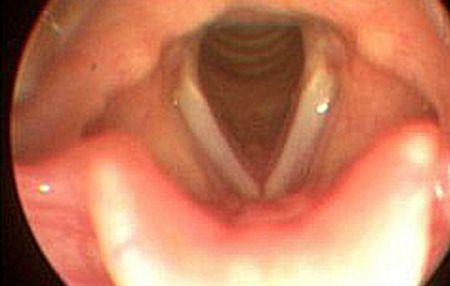

Coarde sau corzi vocale. A o tinea coarda a nu te intrerupe a nu te opri. Coardele vocale sunt două pliuri simetrice ale mucoasei laringelui ridicate de ligamentele vocale astfel. Adijapan 6 aprilie 2006 07 55 eest. Coarde le vocale niste tendoane in git care vibreaza si produc vocea.

Semnele si simptomele pot mima o paralizie a coardelor vocale chiar daca nervii. Nodex ul zice mai mult că în funcţie de sens se spune corzi sau coarde. Corzile vocale creeaza vocea. Cele doua parti posterioare ale corzilor vocale se numesc cartilagii aritenoide.

Dacă crezi că vor exista cititori care vor căuta articolul la titlul corzile vocale putem crea un redirect. De obicei este afectată o singură coardă vocală iar dacă sunt afectate ambele corzi vocale aceasta pune dificultăți serioase procesului respirator și deglutiției. Ligamentele vocale se întind între procesul vocal al cartilajului aritenoid și cartilajul tiroid. Ele sunt legate prin membrana cricovocală de arcul cartilaginos cricoidian ligamentele vocale și membranele cricovocale sunt învelite de mucoasa laringiană.

A atinge pe cineva la coarda simtitoare a l atinge unde l doare unde simte. Pentru sensul de coardă vocală se precizează pluralul coardele vocale. Muschii vocii pot contracta corzile vocale in mod diferit in functie de cum se deschide sau inchide glota.